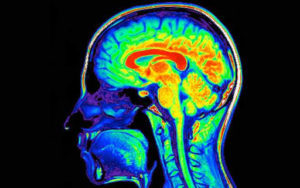

La desintoxicación se refiere al proceso de eliminar las sustancias tóxicas del cuerpo. En el caso de las drogas, significa eliminar las sustancias químicas que alteran el funcionamiento normal del cuerpo.